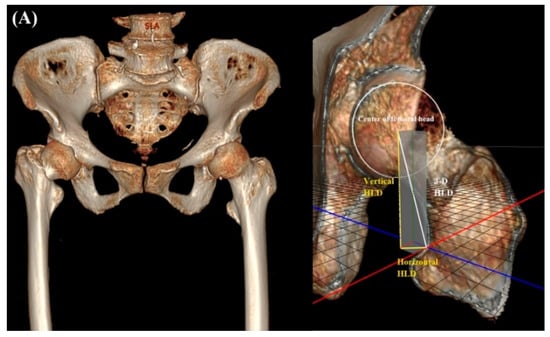

2.2. Radiologic Parameters

| 2-D HLD | 43.4 ± 4.5 | 43.1 ± 3.9 | 0.710 |

| 3-D HLD | - | 45.9 ± 3.6 | N/A |